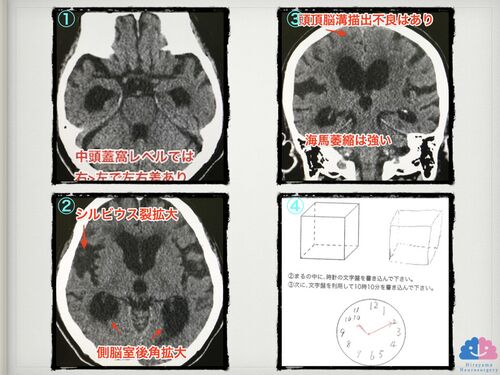

【症例報告】前医でサジを投げられた方に治療介入したところ、半年で家族から「大きく困ることはなくなった」と評価された症例。

「これほど酷い陽性症状の人は、うちでは対応出来ません。紹介状を書くので別の病院に行って下さい」 ベテラン脳神経内科医にサジを投げられ途方に暮れていたご家族。 どのように介入し、改善していったかの一部始終を紹介する。状態変化に寄与したと思われる薬剤は…